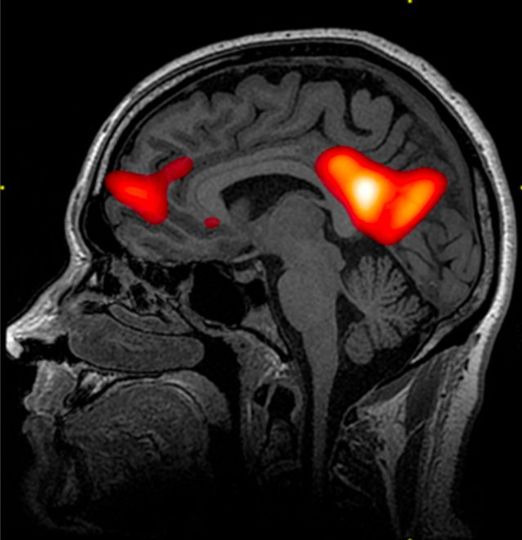

Нужны более сложные методы, такие как функциональное МРТ, которое позволяет посмотреть связь с подкорковыми структурами. И вот здесь мы увидим, что мозг опрашивает соматическую нервную систему.Он буквально горит вашими ощущениями первого свидания, знакомых запахов, он горит приплывом энергии от сказанного «да!», он вспоминает как выглядела эта любовь, какой она была на слух, как приятно ее было трогать, как здорово было прижимать крепко, какие ощущения были вместе в обществе, он вспоминает, как вы сообща преодолевали испытания, он начинает подтягивать в памяти основные моменты вашей общей жизни и пр.

А вот так выглядит влюбленный мозг.